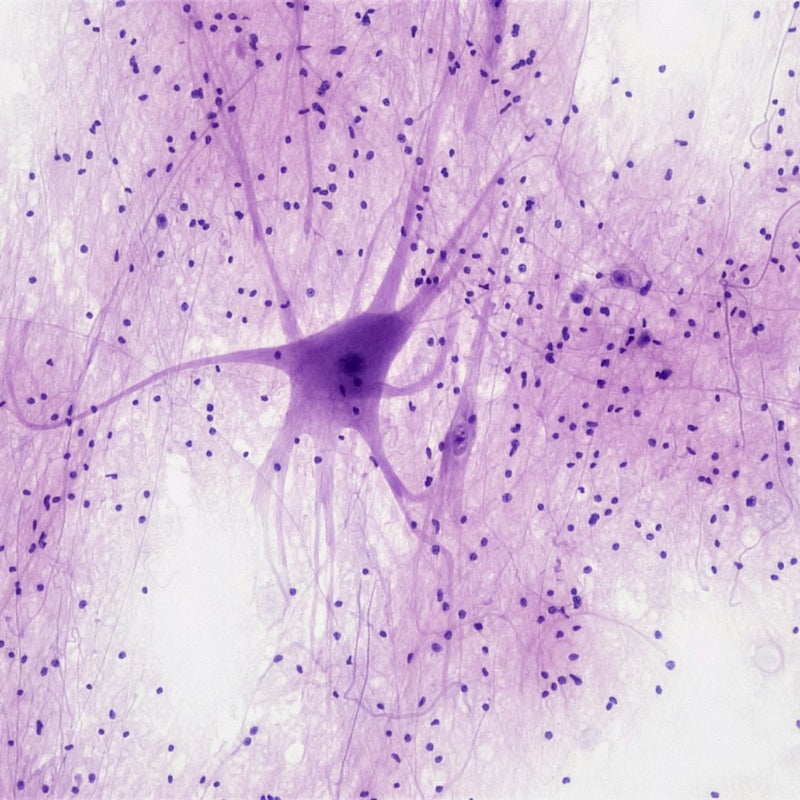

Es ist nicht leicht, neurodivergent zu sein, da unsere Gesellschaft auf neurotypische Menschen zugeschnitten ist. Das Gehirn von neurodivergenten Menschen verarbeitet Reize anders. Heute wird dies nicht mehr als "Störung", sondern als Variante betrachtet, die neben Schwächen in einigen Bereichen auch viele Stärken mit sich bringt. Zu den häufigsten und bekanntesten Varianten zählen ADHS und Autismus-Spektrum-Störungen wie das Asperger-Syndrom. Manchmal werden diese erst im Erwachsenenalter erkannt. Ich kann in meiner Praxis leider keine Diagnostik von ADHS und Asperger durchführen. Oft haben die Betroffenen aber einen hohen Leidensdruck, weil sie sich ihr Leben lang "anders" gefühlt haben. Ich helfe Ihnen dabei, traumatisierende Erfahrungen zu überwinden und Strategien für den Alltag zu entwickeln.